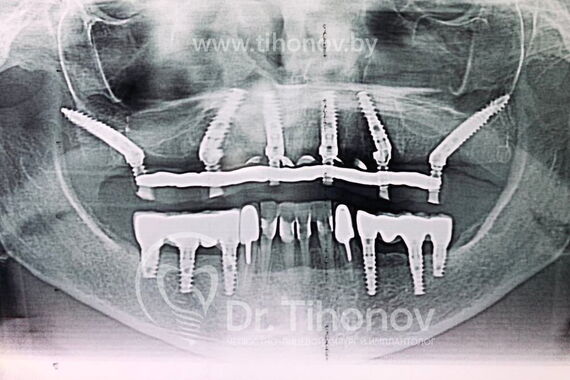

Кейс №5 - Установка 6 имплантов и несъемного протеза за 4 дня

02 Сентября 2020 Установка протеза по методике All-on-6

Решение

На очной консультации после обследования полости рта и изучения данных 3D-исследования челюстей совместно с пациенткой был выработан план реабилитации верхней челюсти с использованием современной и эффективной методики протезирования All-on-6 (все на 6-ти).

Была проведена операция на верхней челюсти, во время которой:

• установлены 6 имплантатов,

• в последующие 4 дня изготовлен и зафиксирован несъемный эстетичный и функциональный протез.

Был достигнут отличный результат, что подтверждается красивой улыбкой благодарной пациентки.